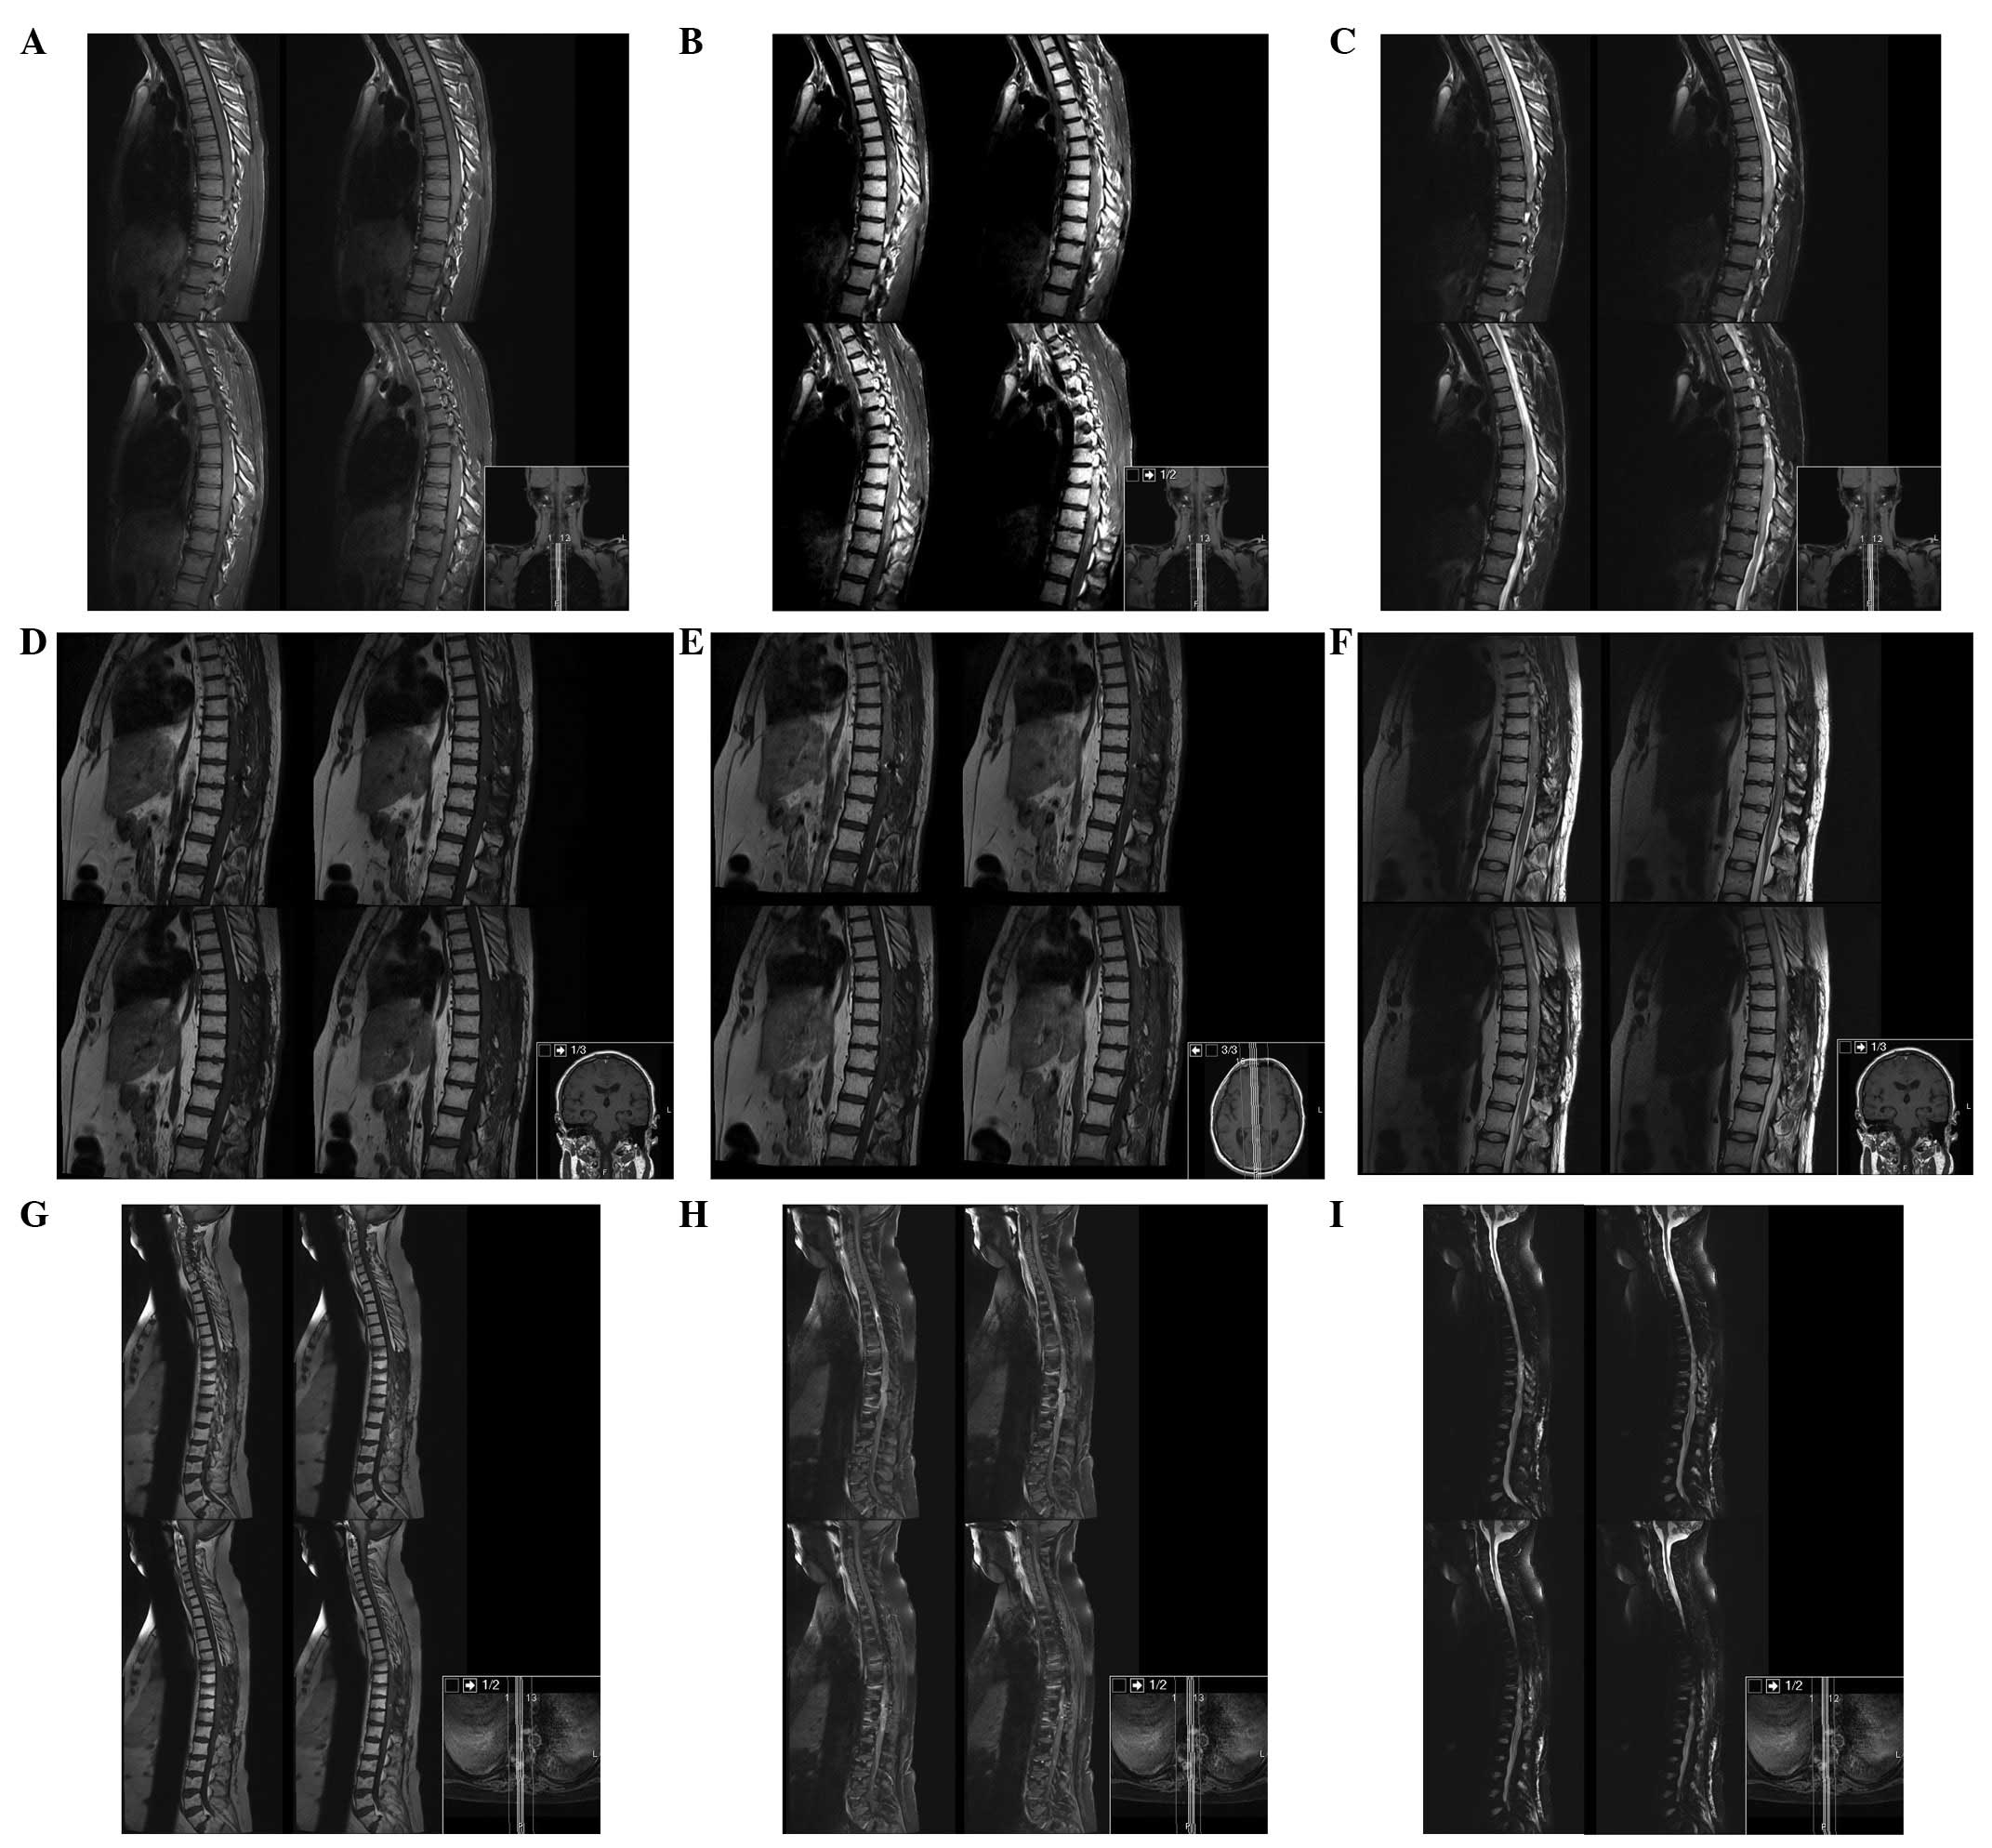

The patient underwent brain and spine magnetic resonance imaging (MRI). The brain and cervical spine were negative for masses and signal intensity alterations, whereas from T1 to L1 there was a marked spinal cord signal intensity and morphology alteration, with notable spinal cord expansion between T6 and T11 and contrast enhancement between T6 and T9 (Fig. 1).

Figure 1

Spine MRI. (A) T1, (B) T1 with contrast and (C) T2-weighted dorsal spine sagittal view MRI at presentation, demonstrating the presence of the tumour between T1 and L1. (D) T1, (E) T1 with contrast and (F) T2-weighted dorsal spine sagittal view MRI 3 months after surgery. (G) T1, (H) T1 with contrast and (I) T2-weighted dorsal spine sagittal view MRI 17 months after surgery, demonstrating enlargement of the enhancing mass from T3 to T12 with subarachnoid metastatic deposit in C2 and C4. MRI, magnetic resonance imaging.

Serial MRI at 3, 6 and 17 months was performed (Fig. 3). Six months after surgery the patient deteriorated, becoming completely paraplegic and losing bladder function. Cranial and spine MRI revealed enlargement of the residual tumour from T3 to T12 with cranial extension of oedema to the obex, and subarachnoid metastatic deposits in C2, C4 and in the pituitary stalk, with hydrocephalus. We proposed cranio-spinal irradiation, but as the patient was stable and without signs or symptoms of increased intracranial pressure (ICP) the patient and his family decided to withhold this treatment and wait.